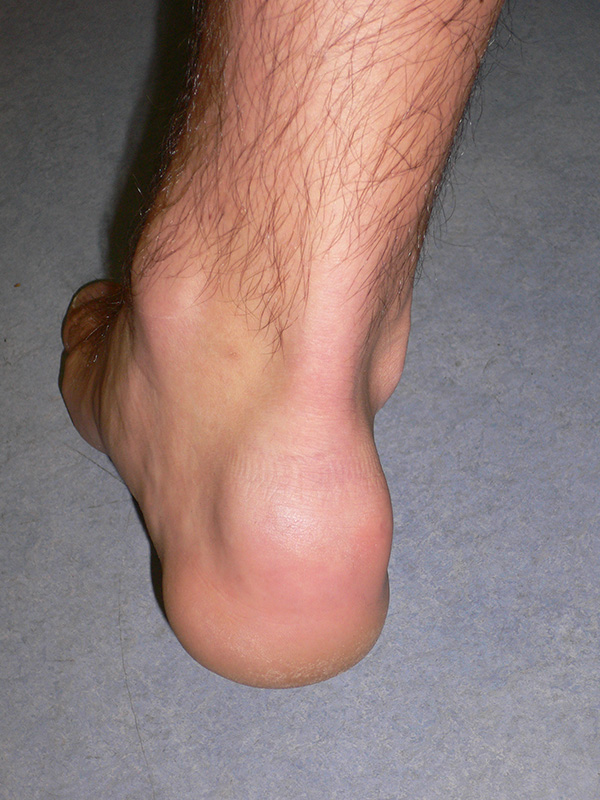

Rückfußachse

Die Längsachse des Fersenbeins weicht gegenüber der Längsachse des Unterschenkels um ca. 7° zur Außenseite ab (physiologischer Rückfußvalgus). Ist die Abweichung vermehrt, liegt ein Knickfuß vor, ist die Abweichung vermindert, oder kommt es gar zu einer Abweichung zur Innenseite, wird dies als Rückfuß varus bezeichnet. Genaue Grenzen, ab wann z.B. ein Knickfuß vorliegt sind nicht definiert. Eine Abweichung zur Innenseite ist aber in jedem Fall pathologisch.

Abbildung 6: Ausgeprägter Rückfußvalgus rechts, hier in Folge einer subtalaren Koalitio (J. Dohle).

Abbildung 7: Ausgeprägter Rückfußvarus rechts (J. Dohle).